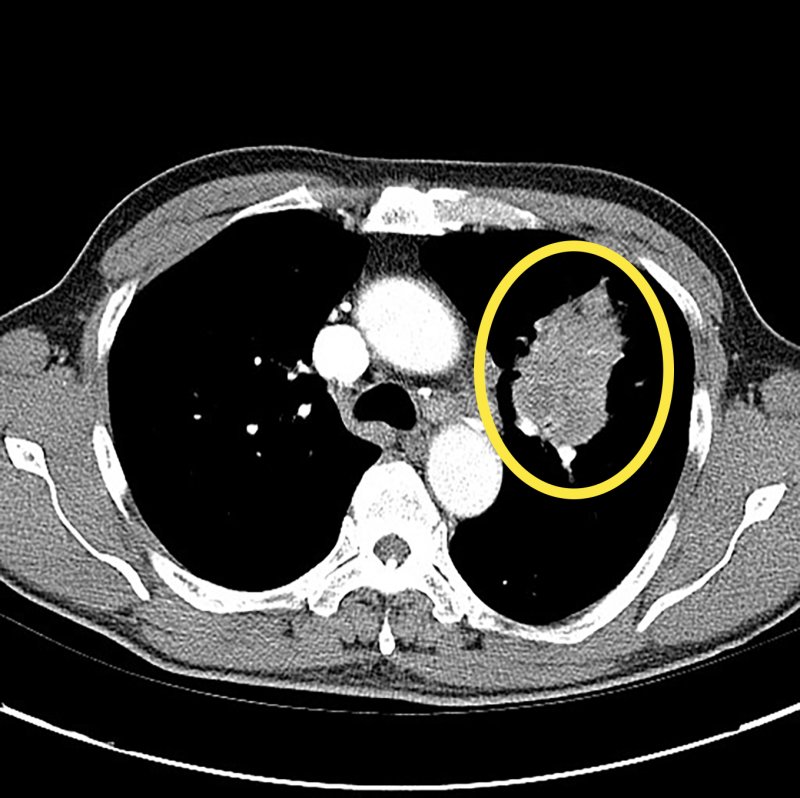

[서울=뉴시스]폐암 환자의 CT검사 사진. (사진= 서울아산병원 제공) 2025.03.14. photo@newsis.com.

[서울=뉴시스] 류난영 기자 = 폐암은 초기에 발견하면 생존율이 크게 높아진다. 특히 조기 암일 경우 폐 기능을 최대한 보존하는 수술로, 생존을 넘어서 수술 후 삶의 질까지 향상시킬 수 있다.